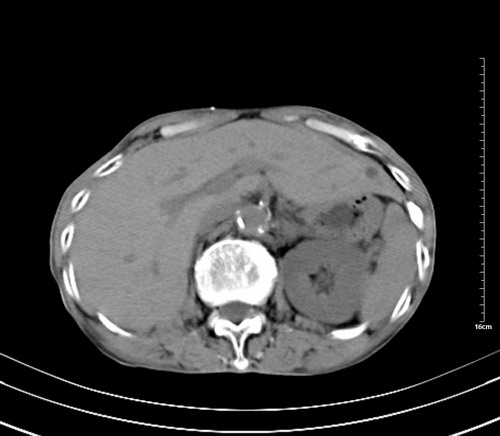

1 气管旁、隆突下淋巴结明显肿大,肝左叶外侧段低密影,都考虑转移。

2 肝右后叶下段明显增大,片状低密影,但因各种伪影显示不佳,不排除病变。

肺癌,纵隔淋巴结转移,肝左叶病变考虑为转移病灶。

后中纵隔团块影,伴气管、食道受压移位,首先考虑转移瘤,肝s5段低密度灶。建议增强检查,另外其结肠是否有问题请提供,右肺部分肺叶局限含气增多,考虑局限肺气肿。

后中纵隔团块影,伴气管、食道受压移位,首先考虑转移瘤,肝表现同11773。